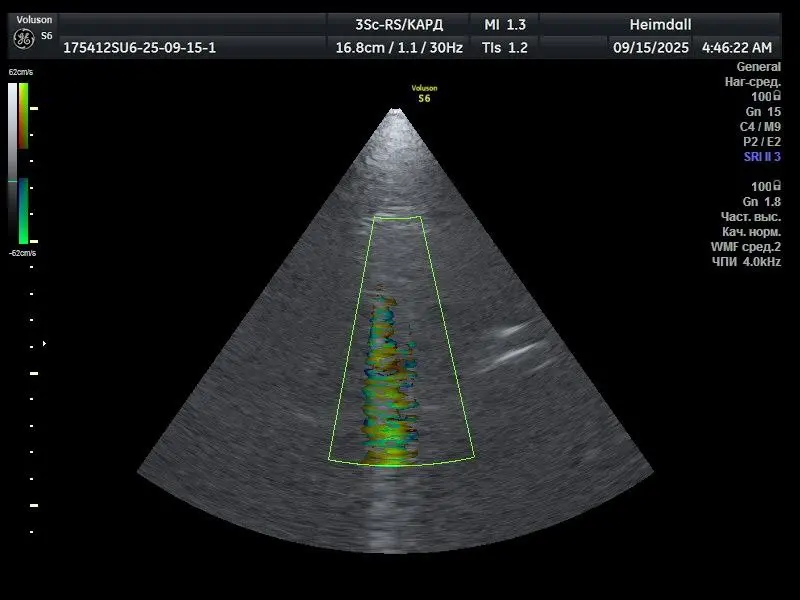

GE 3Sc-RS — фазированный кардиологический ультразвуковой датчик, предназначенный для визуализации сердца и сосудов. Обеспечивает работу в режимах 2D, цветового допплера (C) и импульсно-волнового допплера (PW). Высокая плотность элементов матрицы и фазированная технология требуют стабильной работы всех пьезоэлементов и модулей обработки сигнала. Проблема Пользователь сообщил о полной неработоспособности режимов C и PW. Во всех режимах наблюдались […]

Секторные фазированные датчики активно используются в кардиологических исследованиях, где особенно важна высокая детализация центральной части изображения. Нарушения в работе пьезоэлементов в этой зоне могут полностью исключить датчик из эксплуатации. Модель GE 3SC-RS — одна из популярных в своём классе, но также известна предрасположенностью к износу центрального кристаллического модуля при интенсивной эксплуатации. Сервисная команда Medford провела […]

В наш сервисный центр обратился медицинский кабинет из Читы с типичной для датчиков 3SC-RS проблемой: артефакт в центральной зоне изображения. Повреждение отражалось на клинической точности исследований, а сам датчик не мог использоваться в работе.

Первичный анализ подтвердил предположение: артефакт вызван повреждённым модулем кристаллов. Мы провели замену, выполнили калибровку и тестирование на контрольном оборудовании. После завершения всех процедур изображение восстановилось: чистое, стабильное по всему полю. Аппарат вернулся в эксплуатацию, врач подтвердил, что результат его полностью устраивает.